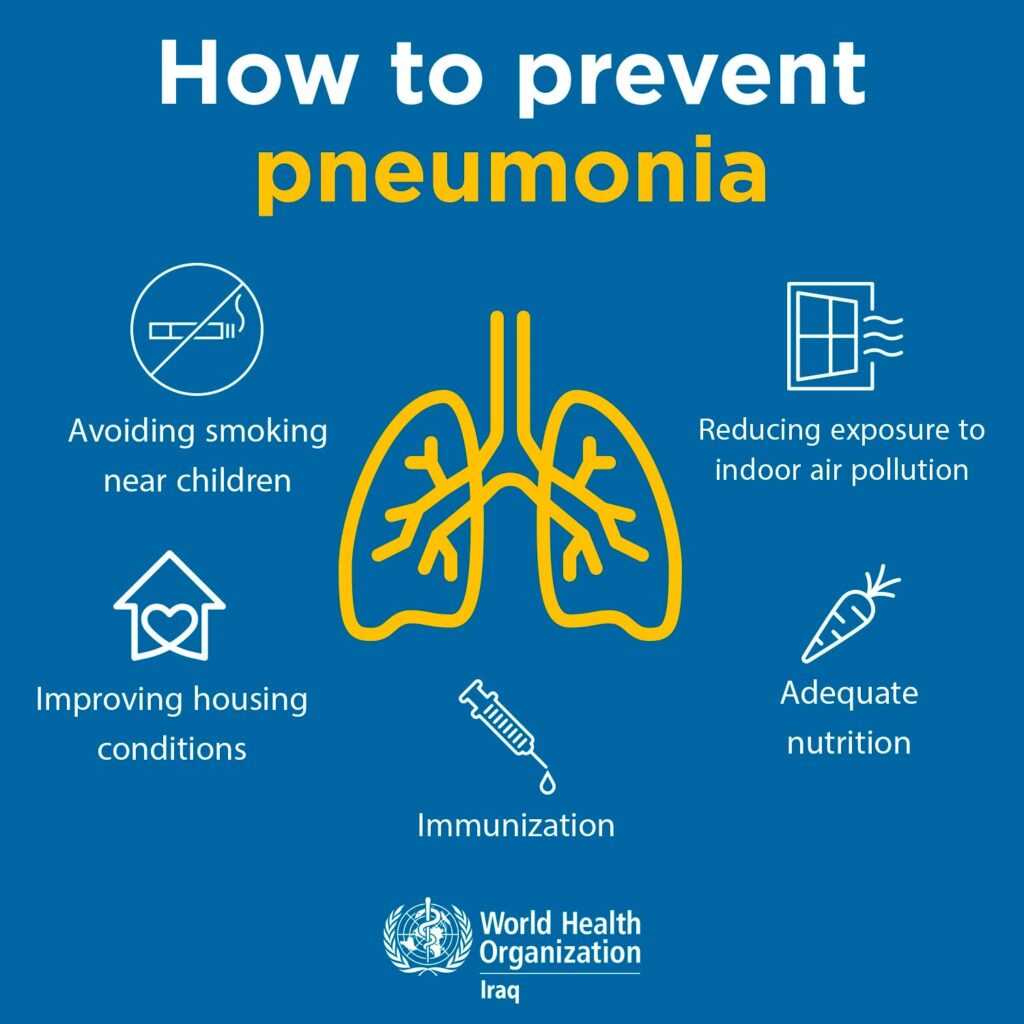

Aumentan enfermedades respiratorias en Oaxaca por bajas temperaturas; autoridades refuerzan llamado a vacunarse

Oaxaca de Juárez, Oaxaca, a 6 de febrero de 2026.— Las bajas temperaturas registradas en los últimos días han provocado un incremento de enfermedades respiratorias en diversas regiones de Oaxaca, principalmente en Valles Centrales, la Sierra Norte y la Mixteca, informaron autoridades del sector salud. De acuerdo con los Servicios de Salud de Oaxaca, durante […]